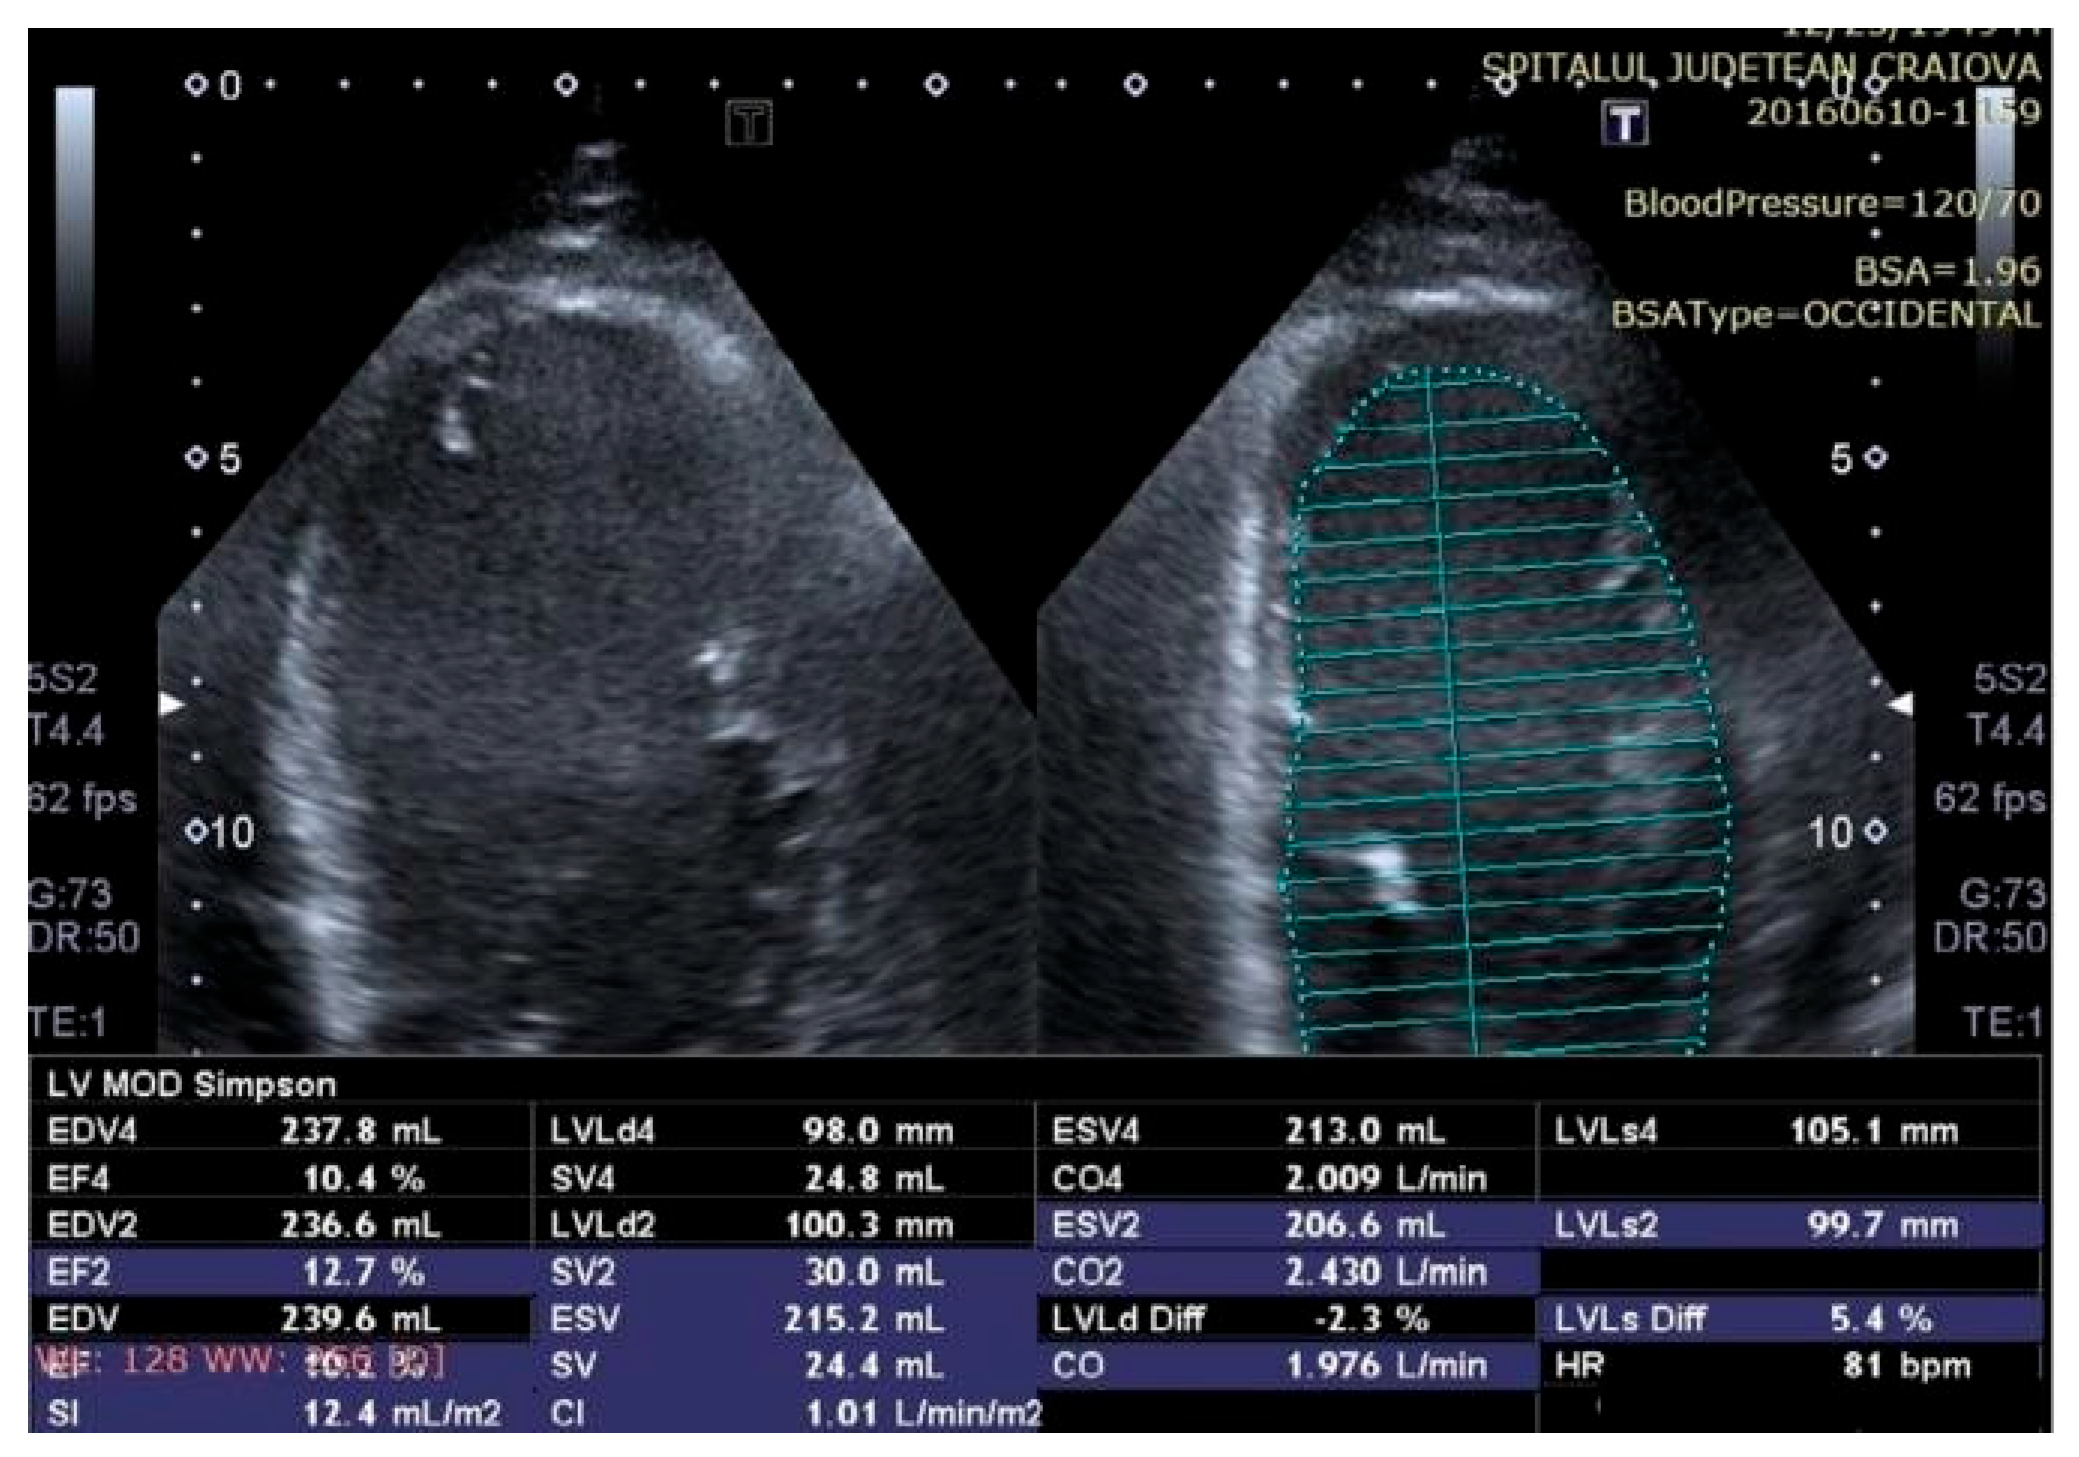

Two-dimensional echocardiography revealed a severely impaired left ventricular (LV) function with a low LV ejection fraction (LVEF) of 10% assessed according to the modified Simpson method, before therapy with a cardiac resynchronization device.

Figure 5.